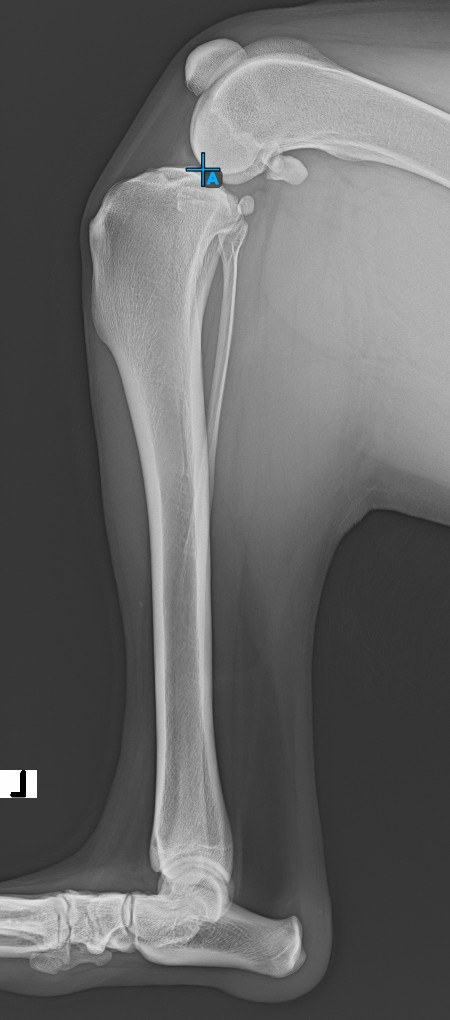

Start the measurement by marking the Eminentia Intercondylaris, which is located on the joint connecting the femur and the tibia.

The image below depicts the usual placement of the Eminentia Intercondylaris point.